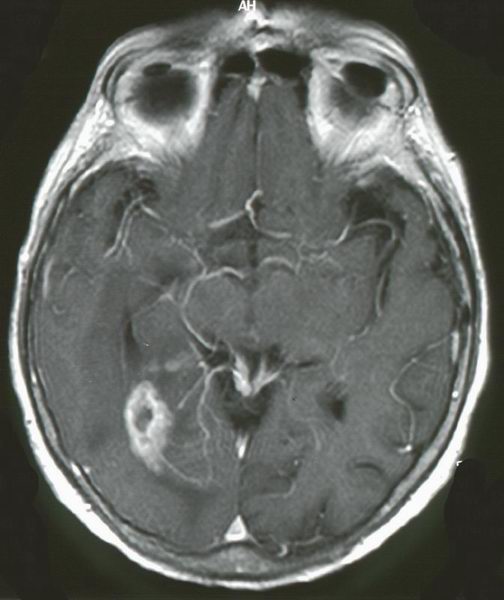

Epidemiologie | Gehirn und Nervensystem können eine Vielzahl unterschiedlicher Tumore bilden. Das MRT zeigt ein kleinzelliges Glioblastom rechts temporo - occipital. Die Randbezirke des Tumors nehmen intensiv Gadolinium auf. |